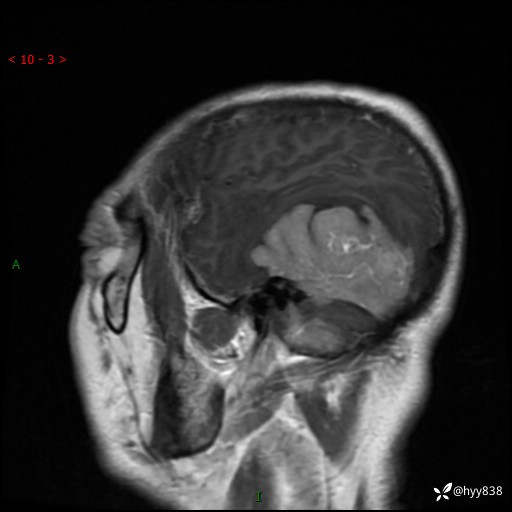

患者性别:男

患者年龄:56岁

简要病史:外院CT提示脑膜瘤,为进一步诊治来我院

临床诊断:颅脑占位

颅脑MRI平扫+增强